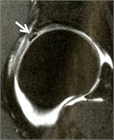

1. 単純X線撮影と読影のポイントを追加し、大腿骨寛骨臼インピンジメント(FAI)の疫学・関節症性変化への進行に関する最新の文献を参考に加筆した。

1. 世界的にコンセンサスの得られた大腿骨寛骨臼インピンジメント(femoroacetabular impingement:FAI)の明確な診断基準はない(エビデンスランクJ)。

1. わが国における狭義のFAI診断指針が提唱されている(エビデンスランクJ)。